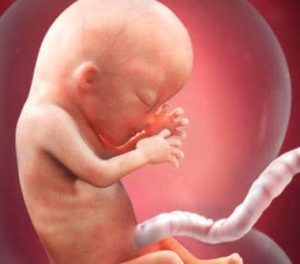

I och med den 13:e veckan av graviditeten börjar en ny trimester. Det innebär ett stort steg för den lilla i din livmoder. I 13:e veckan av graviditeten är din bebis mellan 6,5-10 cm lång och dess vikt är troligen mellan 13-20 gram.

I dess ansikte börjar man kunna urskilja dess unika anletsdrag. Detta, och de andra transformationerna som bebisen genomgår, tittar vi närmare på nedan. Det är oerhört spännande!

Inte bara har dess ögon och öron fått sina slutliga platser, utan en annan riktigt fascinerande detalj kan också observeras: fostrets fingeravtryck finns redan där.

Hjärnan är en av de mest utvecklade delarna av fostret, liksom strukturerna som stöder och täcker organen.

Vid denna tidpunkt utgör huvudet hälften av fostrets totala storlek.

Från och med nu börjar kroppen växa snabbare för att komma ikapp och därmed bilda en proportionell kropp.

Faktum är att vid födseln representerar huvudet endast en fjärdedel av den totala storleken. Dessutom finns det också några mycket viktiga processer relaterade till fostrets kropp och dess funktion som utvecklas under denna vecka.